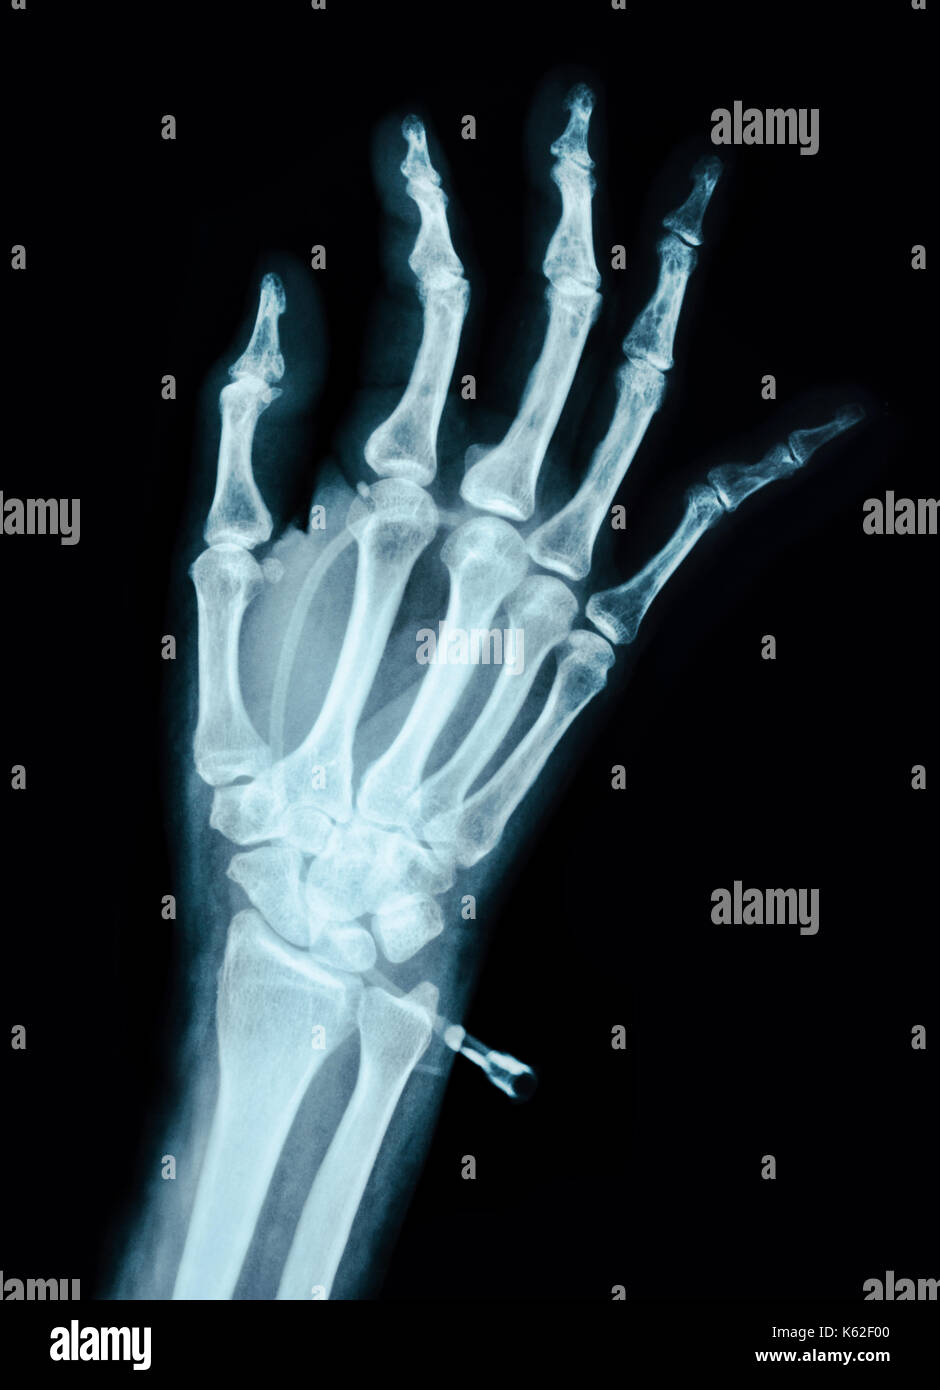

Left Hand X Ray . The pa hand view is requested for diagnosing a variety of clinical indications such as rheumatoid arthritis, osteoarthritis, suspected fracture or dislocation and localizing. Although additional radiographs can be taken. The hand comprises the metacarpal and phalangeal bones. The oblique hand view is requested for diagnosing a variety of clinical indications such as rheumatoid arthritis, osteoarthritis, suspected fracture or dislocation and localizing. The hand series consists of posteroanterior, oblique, and lateral projections. Fractures and dislocations are usually straightforward to identify, so long as the potentially injured bone is fully visible in 2 planes. It uses a small amount of.

Archive Of Unremarkable Radiological Studies Left Hand XRay Stepwards